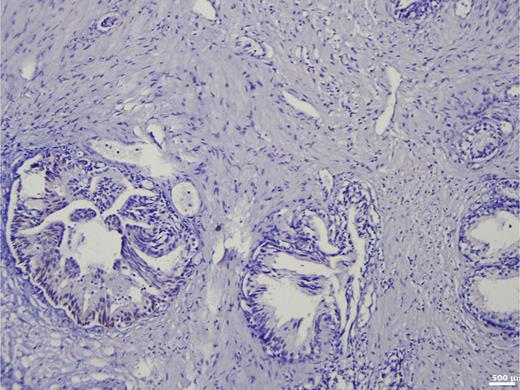

These results are presented in Table 12. The relationship between ISUP grading and BSP expression is illustrated in Table 13 and Figure 6:

In the nonmetastatic group, BSP expression correlated significantly with ISUP grade (r = 0.329; pSR < 0.001).

In the metastatic group, no correlation was found (r = 0.011; pSR = 0.919).

Mean BSP values per ISUP group further illustrate this trend.